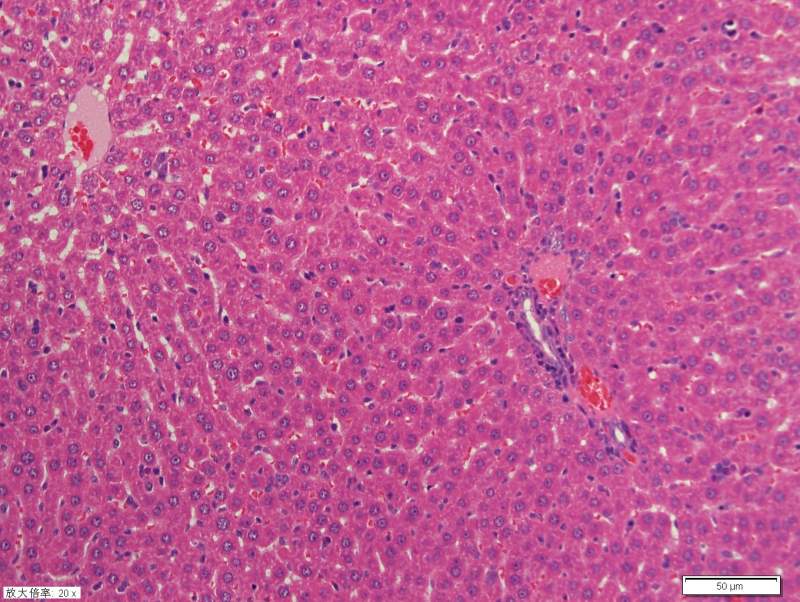

Çó¸÷λսÓѰïæ¿´¿´ÎÒÕ⼸×é¸ÎÔàHEȾɫ½á¹ûÊÇ·ñ·¢ÉúÁ˲¡±ä ûÓÐѧ¹ý²¡Àí£¬ÕæÐÄ¿´µÄһͷÎíË®¡£¡£¡£Íû¸ßÊÖÖ¸½Ì£¬²»Éõ¸Ð¼¤ 1-1.jpg 2-1.jpg 3-1.jpg 4-1.jpg 5-1.jpg 6-1.jpg 11-1.jpg |

| ÓÐÑ×֢ϸ°û£¬µ«ÊÇ¿´ÆðÀ´ÏñÊÇÕý³£¸ÎÔà×éÖ¯£¬ÁíÍ⣬ÇÐÆ¬ÓпªÁÑÏÖÏ󣬿ÉÄÜÊÇÄãʹÓõÄ×éÖ¯¹Ì¶¨ÒºÓÐÎÊÌâ¡£ |